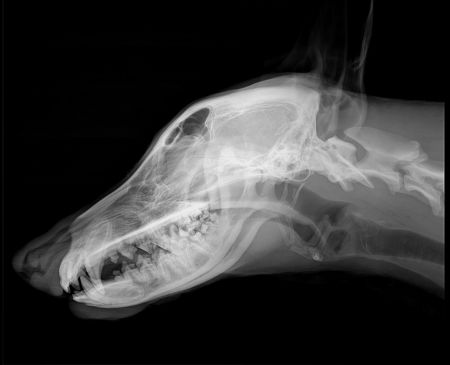

Craniu